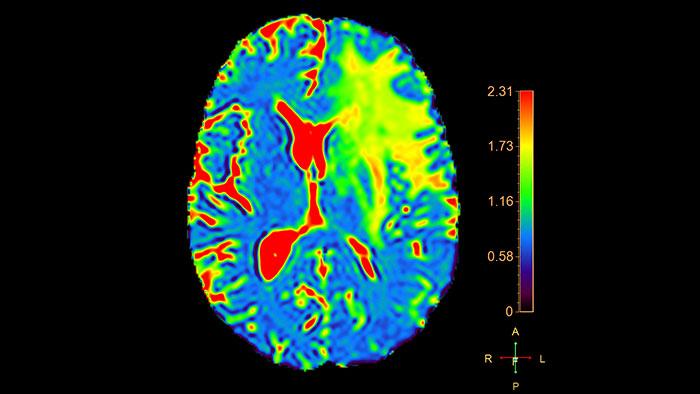

T2* (Neuro) Perfusion

MR T2* (Neuro) Perfusion

Reviewing brain tissue perfusion viability

Provides physicians with supporting information for the evaluation of stroke, or assessment and follow-up of brain tumors. The application supports the analysis of T2* Perfusion studies to generate parametric data including TTP, MTT or Tmax.

• Offers several analysis techniques such as leakage correction, which allows to assess the time intensity curves where there is no proper recovery of the baseline after contrast passage, and manual arterial input function (AIF) which enables perfusion-diffusion mismatch if a Diffusion input dataset is available in addition to the Perfusion series.

• The package includes user-selected color coding of the functional data, and maps can be viewed and stored as overlays on anatomical reference images.